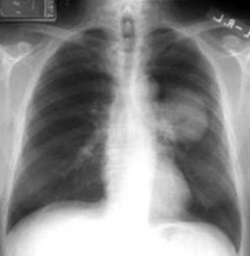

¿Cuál es el diagnóstico?

Bronquiectasias